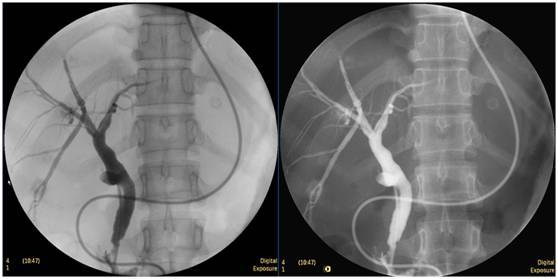

C臂旋轉(zhuǎn)多角度觀察

在內(nèi)徑與膽管、腸氣等結(jié)構(gòu)圖像重疊時,只需旋轉(zhuǎn)C臂即可將重疊的影像分開觀察,避免讓患者翻身造成內(nèi)徑脫落的風(fēng)險。

鼻膽管造影

立位注入造影劑,膽總管顯影好,稍擴張,未見結(jié)石影。